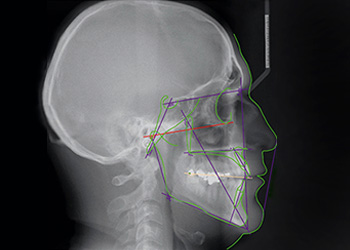

IMÁGENES 2D

Alta resolución con equipos de última generación

Rx Extraorales e Intraorales